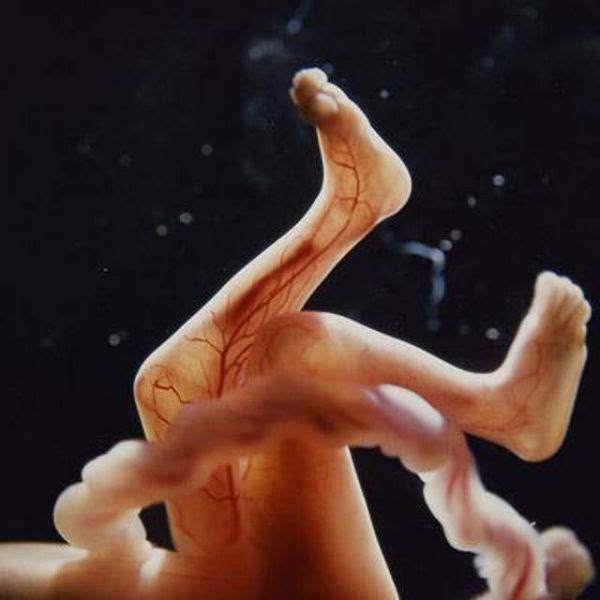

15. 到了16週時,胎兒開始會用雙手摸摸自已的身體,和探索周邊環境。

16.這時胎兒的骨骼都是由軟骨所構成的,我們能夠從薄薄的皮膚當中,清楚看到血管的分佈。

17. 懷孕18週,胎兒大小大約有14公分,這時他們也可以聽到外界的聲音啦!